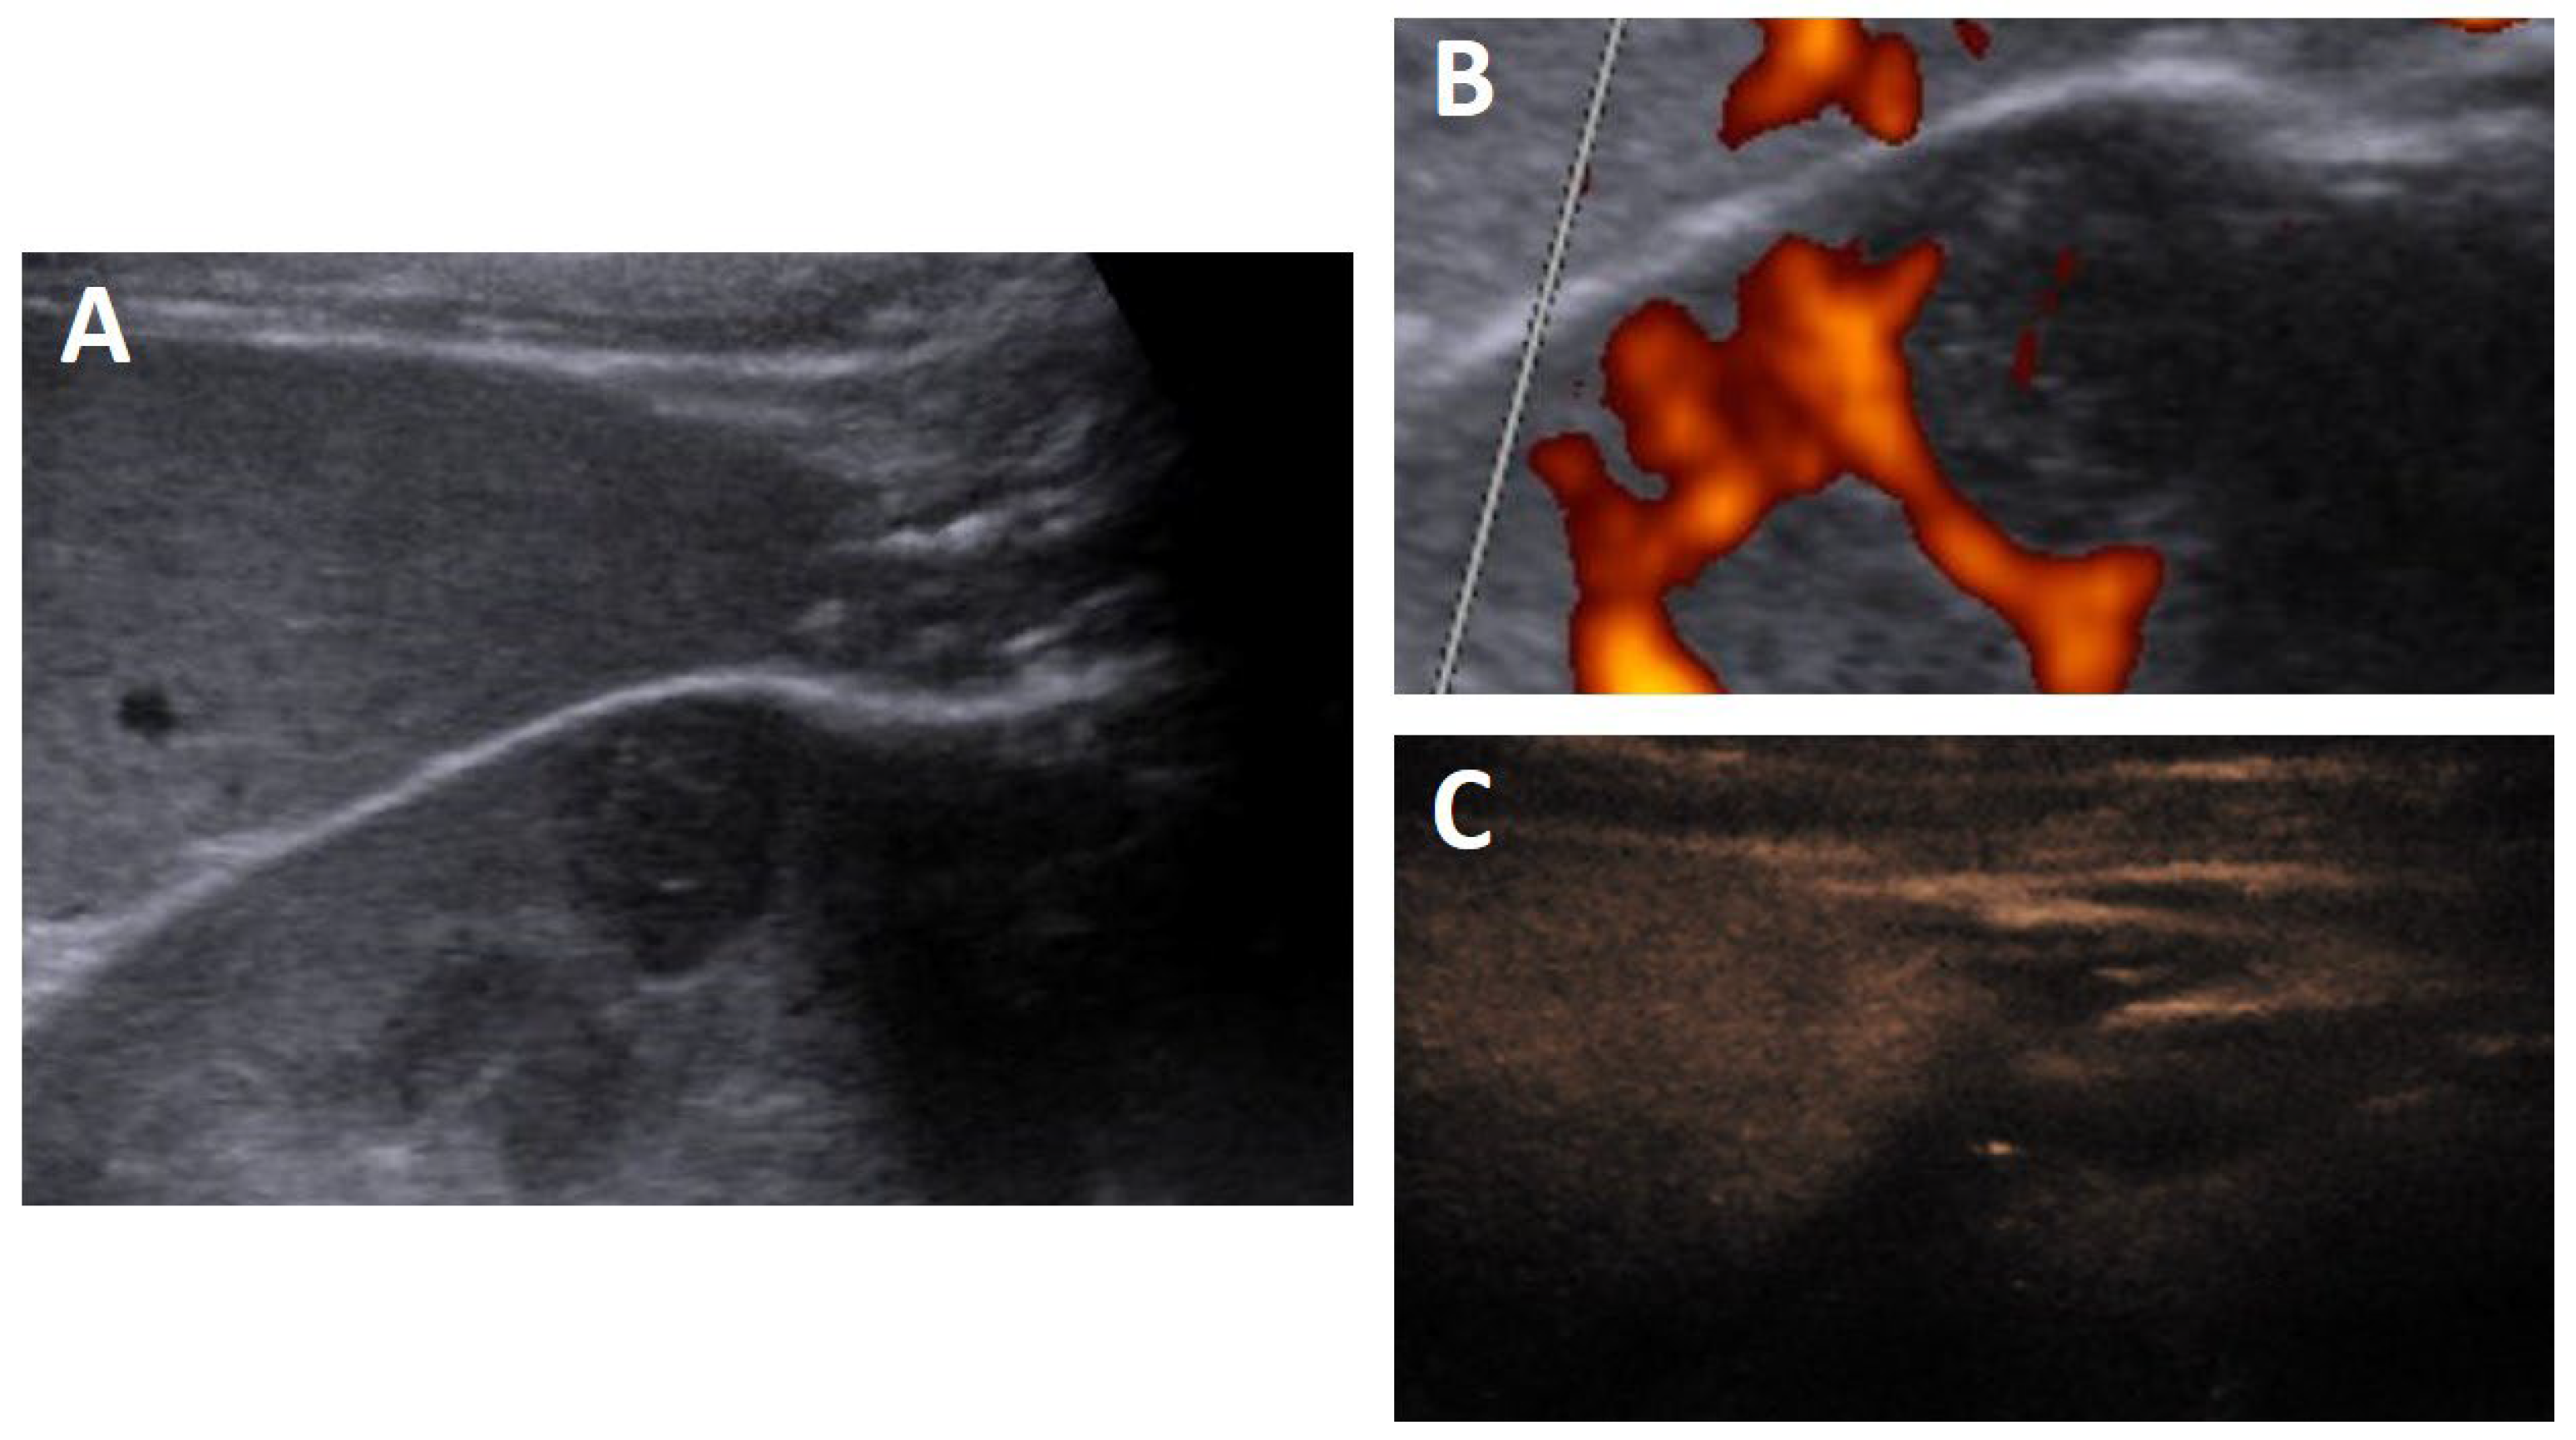

2. Case Study